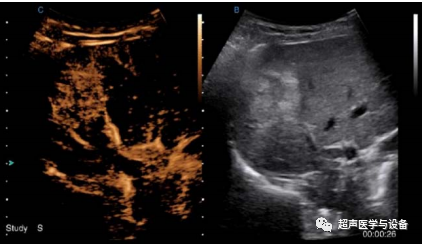

智灵造影成像

通过通过智灵算法将造影剂增强血液的背向散射,使血流清楚显示,可以实现

血流连续谐波成像,也能减少组织谐波的干扰,从而帮助临床进行鉴别诊断目的。应用优势:

▶ 灵敏度高、分辨率好;

非造影信号抑制能力强;

双实时:实时显示组织图像和造影图像;

支持计时及造影击碎功能